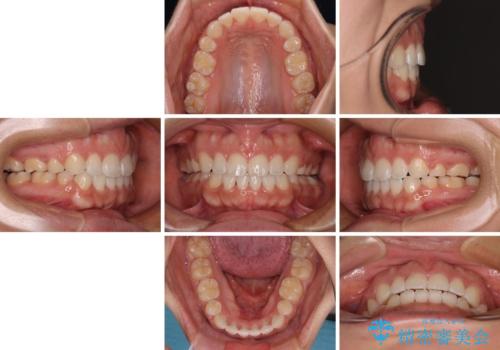

- 20代女性

- メタルブラケット

- 3年1ヶ月

上下前歯部の被蓋関係を改善するの時間がかかり、3年間を要することとなりましたが、スッキリとした口元に仕上がりました。